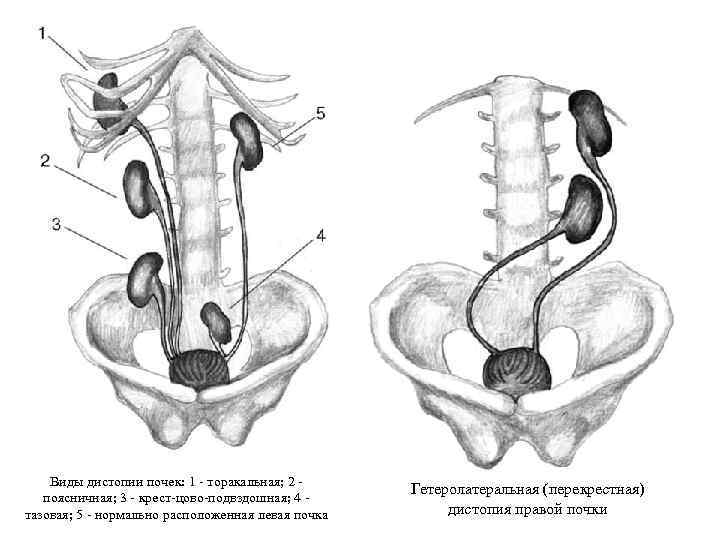

Аномалии расположения и формы почек Дистопия почек: односторонняя (грудная, поясничная, подвздошная, тазовая); перекрестная. Сращение почек: одностороннее (L-образная почка); двустороннее (подковообразная, галетообразная, асимметричные - L- и Sобразные почки).

Аномалии расположения и формы почек Дистопия почек: односторонняя (грудная, поясничная, подвздошная, тазовая); перекрестная. Сращение почек: одностороннее (L-образная почка); двустороннее (подковообразная, галетообразная, асимметричные - L- и Sобразные почки).

Виды дистопии почек: 1 - торакальная; 2 поясничная; 3 - крест-цово-подвздошная; 4 тазовая; 5 - нормально расположенная левая почка Гетеролатеральная (перекрестная) дистопия правой почки

Виды дистопии почек: 1 - торакальная; 2 поясничная; 3 - крест-цово-подвздошная; 4 тазовая; 5 - нормально расположенная левая почка Гетеролатеральная (перекрестная) дистопия правой почки